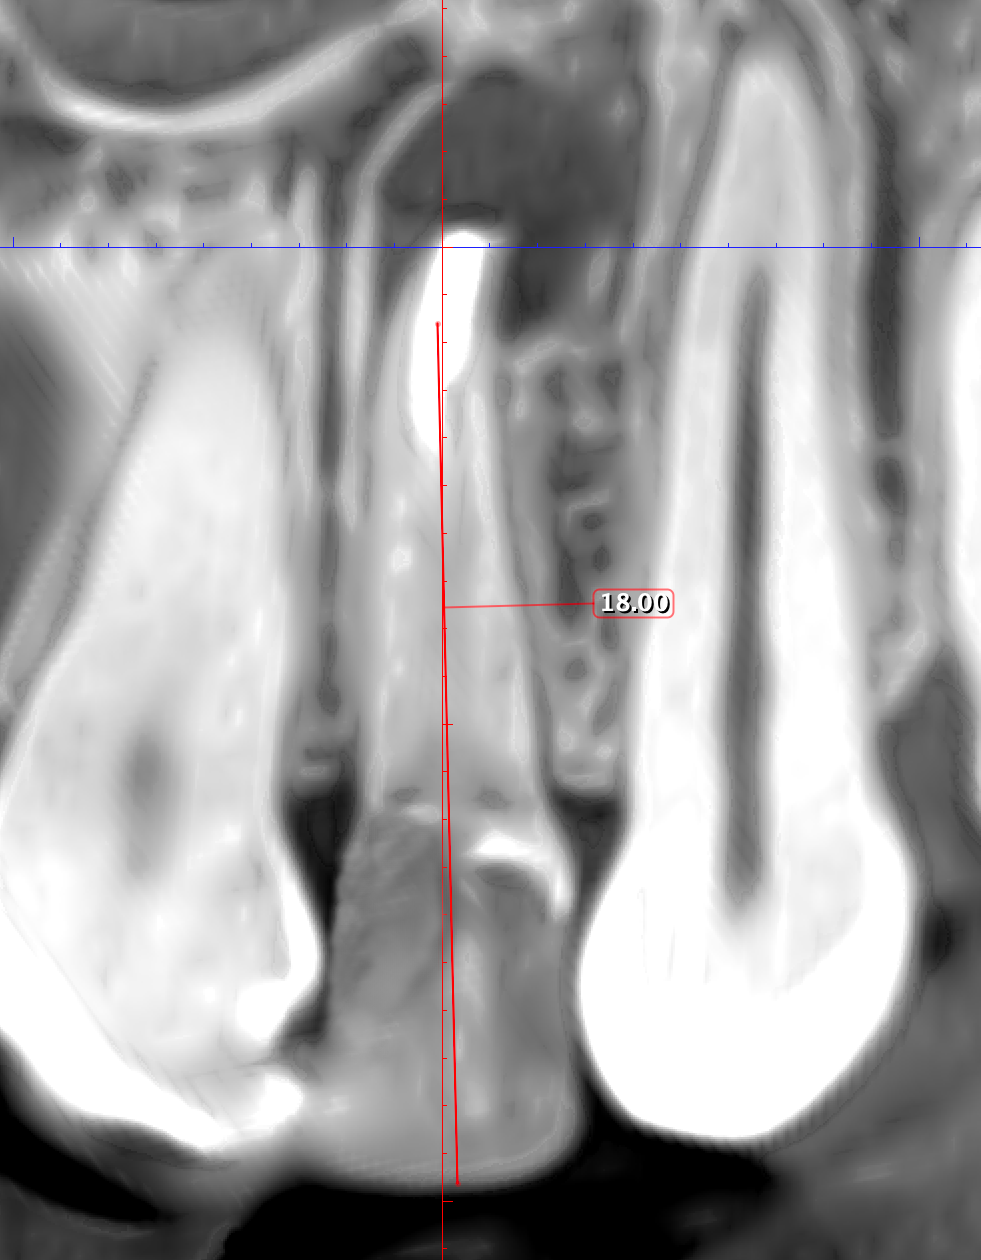

Therefore, the selection of this type of incision requires thorough treatment planning [12]. To avoid the incision falling into an existing bone defect or a defect created by an osteotomy, it is rational to plan a submarginal incision. We can determine whether we can make it, according to the clinical situation of a patient by following approach. To do this, first we need to determine on the CBCT where the bone defect is located or where the osteotomy will take place. Then, using a virtual ruler, measure the distance from the incisal edge of the tooth on which the intervention will be performed to the beginning of the bone defect or osteotomy (Fig 7).

We transfer this distance is transferred to a metal probe and fixed with an endodontic stopper. Next, we take a plastic probe and substitute it near the zenith of a tooth on which the intervention will be performed at a mark of 6 mm (3 mm must be retreated to perform a submarginal incision and another 3 mm is needed for the formed flap to overlap healthy bone tissue) (Fig 8).